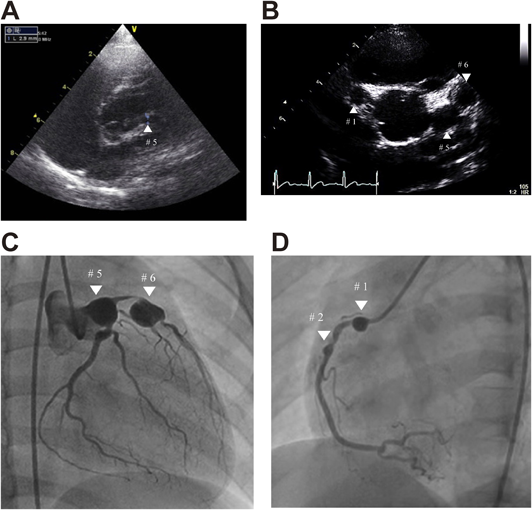

Fig. 1 Echocardiographic and angiographic findings in Case 1

(A) Echocardiogram performed in Case 1 during the acute phase of Kawasaki disease at a local hospital. Retrospectively, only the proximal part of the left coronary artery could be visualized (white ▲). (B) Echocardiogram in Case 1 performed at school cardiac screening. The parasternal short axis of the aortic root demonstrated the presence of bilateral coronary artery aneurysms (white ▲). The diameter of the right coronary artery aneurysm was 7.4 mm at #1 and those of left coronary artery aneurysms were 9.1 at #5 and 9.5 mm at #6, respectively. (C) Left coronary angiography in Case 1 demonstrating coronary artery aneurysms of 10.7 mm and 12.3 mm in diameter at segment 5 and segment 6 (white ▼), with a 99% stenosis between the aneurysms. (D) Right coronary angiography in Case 1 demonstrating coronary artery aneurysms of 6.6 mm and 3.1 mm in diameter at segment 1 and segment 2 (white ▼).

2012年5月(6歳),KD既往で定期フォローされていなかったため学校心臓検診2次検診の心エコー図検査(Fig. 1B)を施行され,右冠動脈#1に径7.4 mmの冠動脈瘤と左冠動脈#5, 6にそれぞれ径9.1 mmと9.5 mmの数珠状冠動脈瘤を指摘された.精査目的で前医を受診し,心エコー図検査・造影CT検査で,segment(S)1, 5, 63)に巨大瘤,S6に99%狭窄が認められ,アスピリン・ワーファリンの内服が開始された.アデノシン負荷テクネシウム心筋血流シンチグラフィで前壁中隔の虚血所見も認められ,経皮的冠動脈形成術(percutaneous coronary intervention: PCI)施行目的で2012年6月に当院へ入院した.

経過